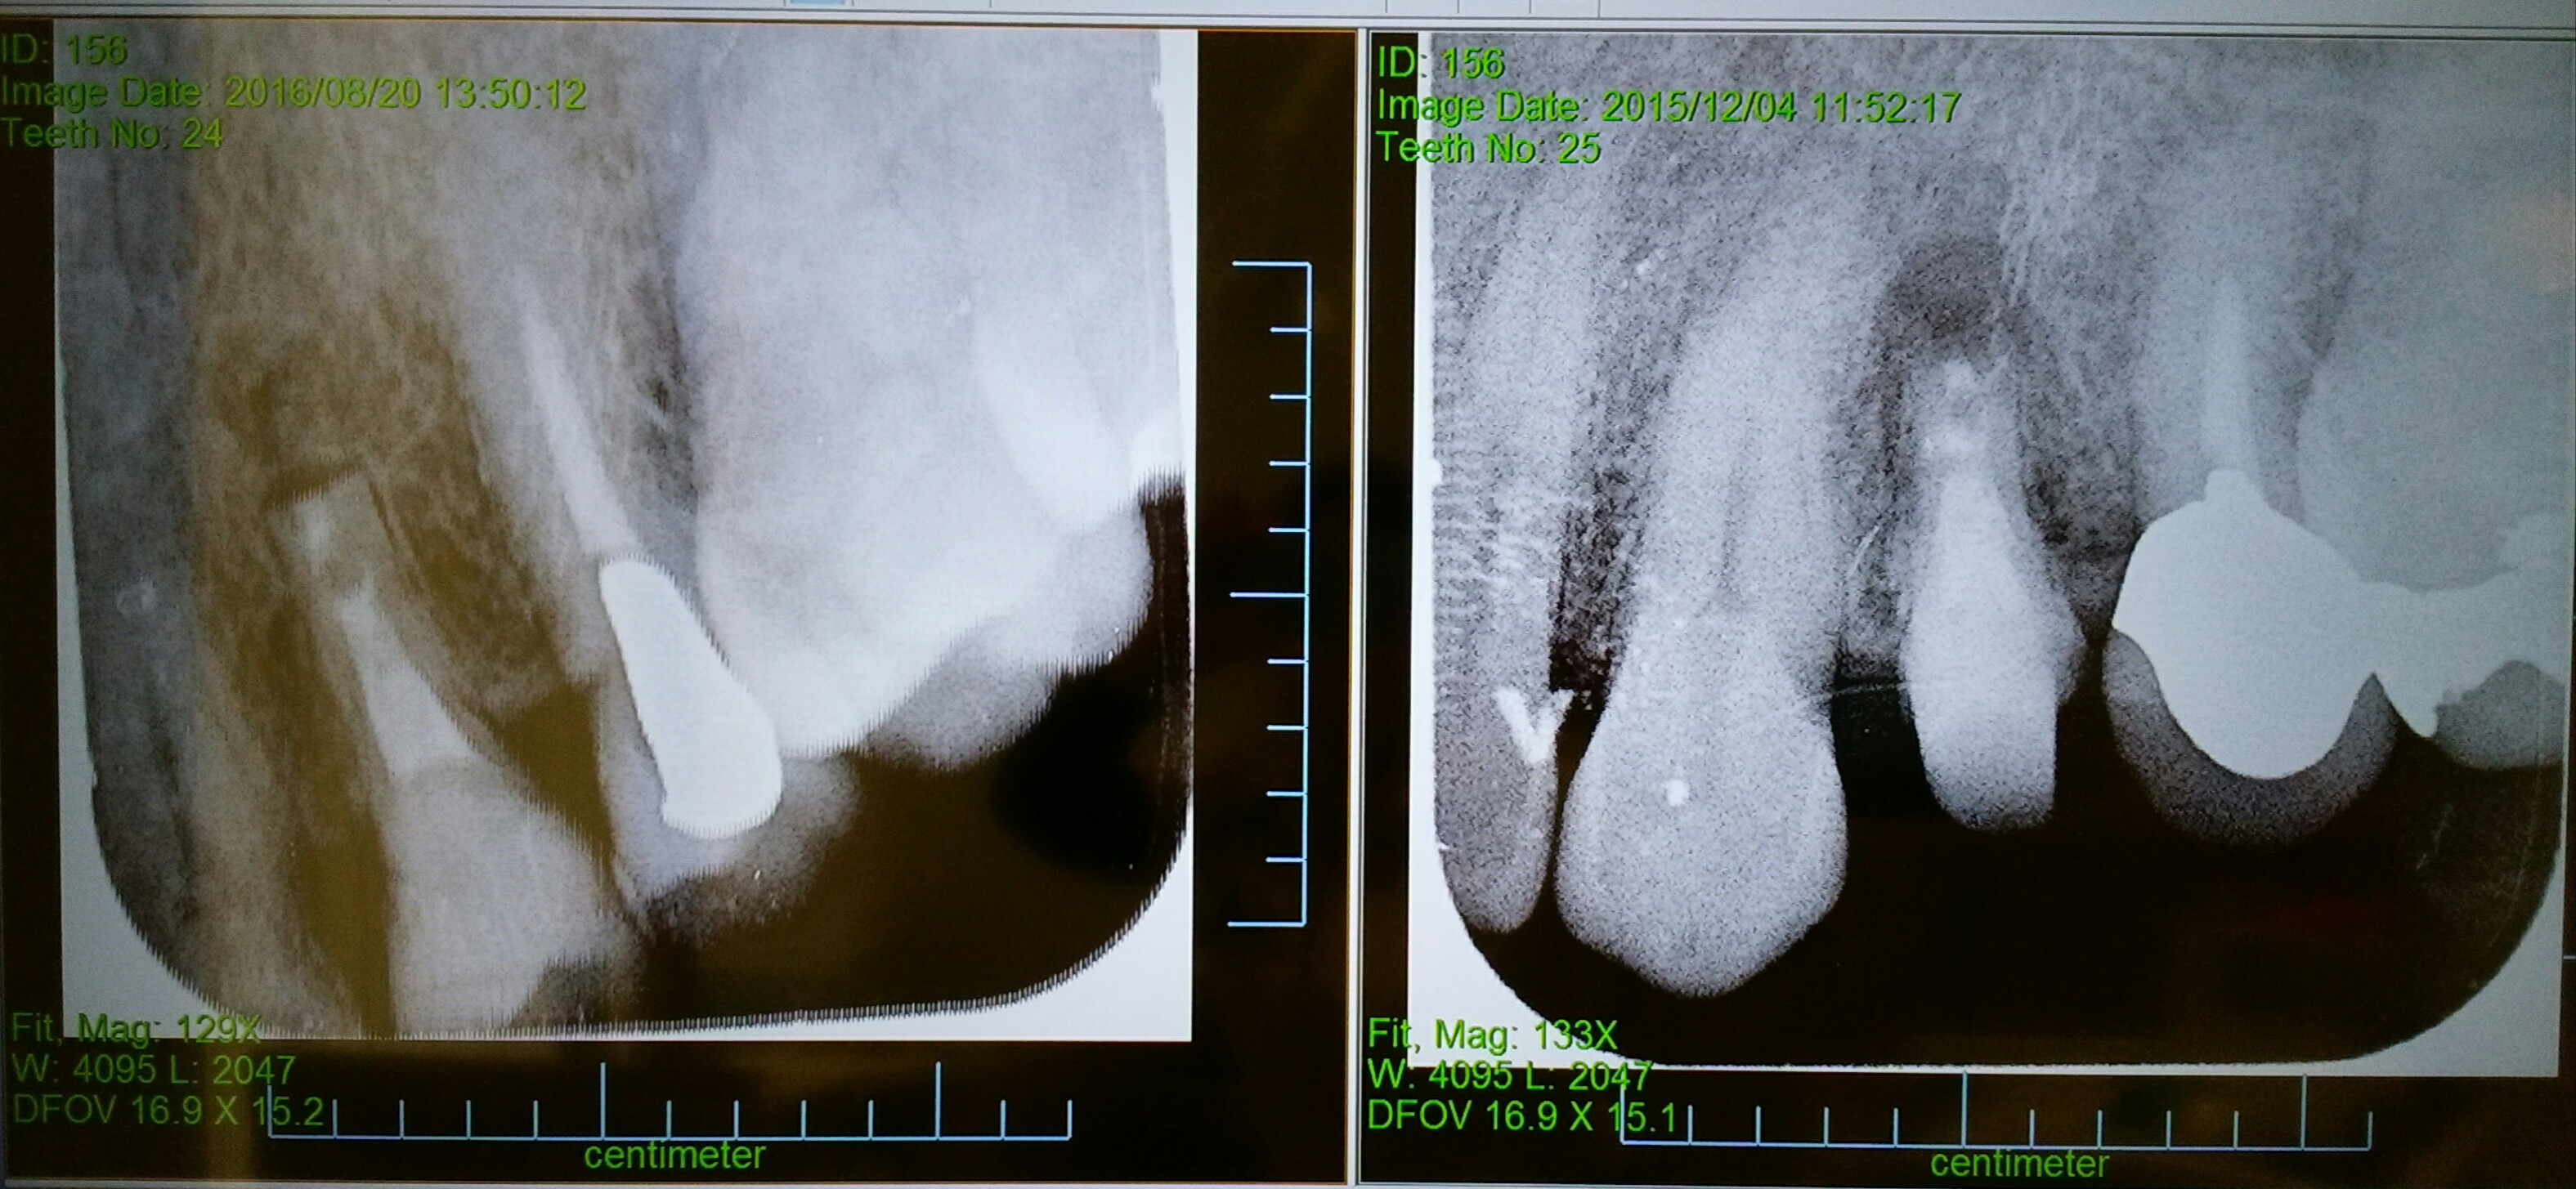

2015年12月に根っこの先を切り取りました。

2016年8月に同じところを確認のレントゲンを撮りました。

しっかりと骨が埋まってきています。